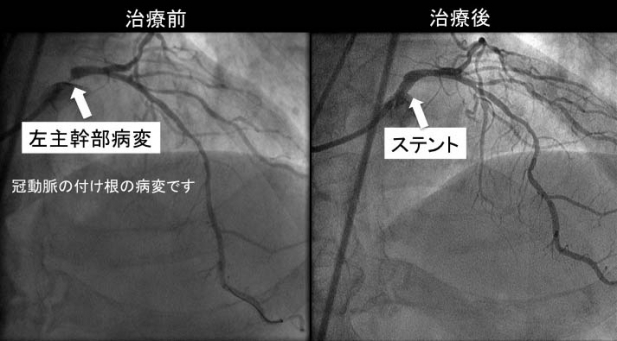

70代の男性が4ヶ月前から歩行時に胸が痛むとのことで来院されました。症状の特徴、持続時間、誘因、発生状況などから“狭心症”に間違いありません。問題は診断名ではなく、その重症度にあります。今すぐ緊急入院にすべきか、緊急ではなくとも早めに入院すべきか、或いは外来でよく調べてからにするかなど、重症度によって治療の進め方が違ってきます。さて、この患者さんですが、重症狭心症の“ニオイ”がしました。すぐに入院して精密検査を受けるようにお勧めしたところ、翌日から家族で旅行に行く予定だからすぐに入院はできないという返答です。悩ましい状況です。結局ご本人と相談の結果、即刻薬による治療を開始、1泊旅行から戻ったその日に当クリニックを再受診していただく約束で旅行に出かけていただきました。幸い旅先では症状もなく、お孫さんと楽しい時間を過ごされたようでした。翌週榊原記念病院に入院していただき、私自ら心臓カテーテル検査、冠動脈(心臓に栄養を供給する大切な血管)造影を行いました。左主幹部という冠動脈根本の太い部分にきつい狭窄が存在するという最重症の狭心症でした。直ちにステントという狭窄を拡げる器具を植え込み無事治療が終了しました(図)。その後患者さんの狭心症症状は完全に消失し、現在も元気に通院されていらっしゃいます。